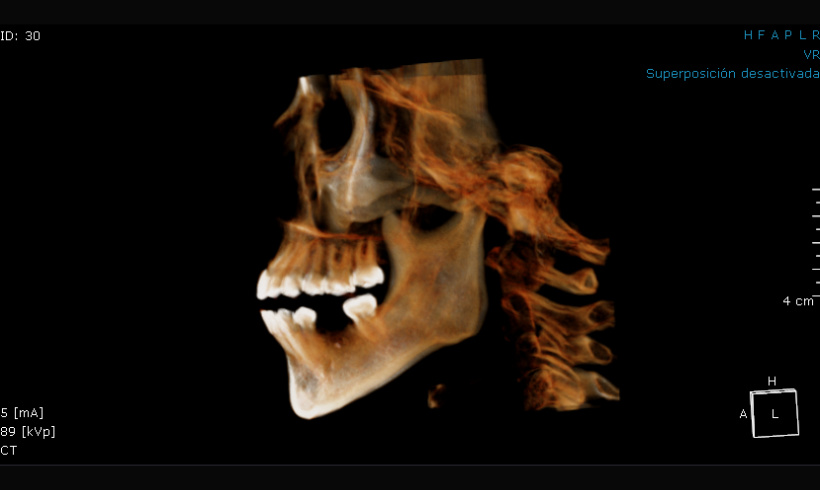

La tomografía, junto con el escaneo nos permite realizar guías quirúrgicas para la colocación de implantes, alargamiento de coronas, colocación de mini implantes de ortodoncia, tratar endodóndicamente dientes calcificados.

Tomografía para guías quirúrgicas